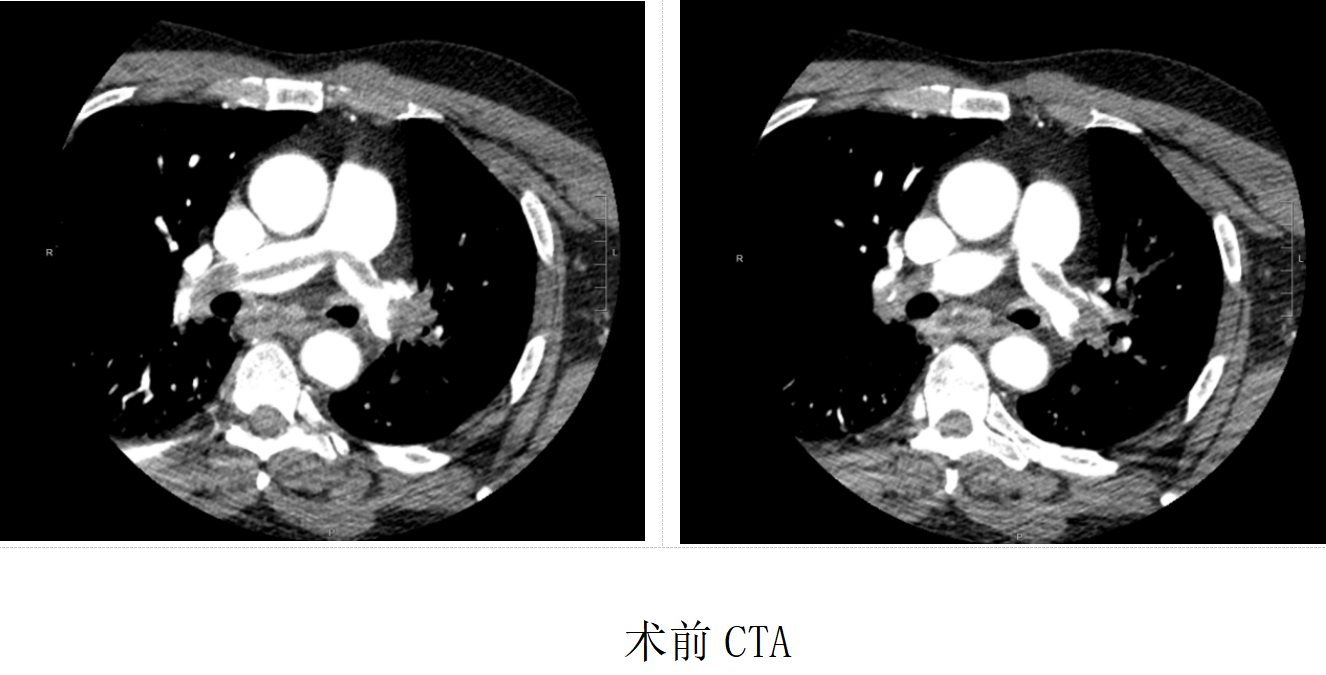

急诊科立即完善头颈部CTA+CTP,并同步加做肺动脉检查,最终明确诊断为急性肺动脉主干骑跨栓,血栓堵塞肺部“呼吸命脉”,随时可能心跳呼吸骤停。

确诊即下达“生死令”。患者病情危重、缺血缺氧明显,转院途中风险极高,且暂无ECMO支持,急诊介入手术难度极大。介入团队迅速启动MDT会诊,与家属充分沟通后,果断实施左下肢静脉造影+下腔静脉造影+肺动脉造影+肺动脉溶栓+取栓+下腔静脉滤器置入的一站式介入手术。

术中患者突发抽搐、氧饱和度仅86%,团队立即全麻稳定生命体征。造影证实左下肢漂浮血栓为源头,肺动脉主干骑跨血栓致左肺上叶动脉完全闭塞。溶栓、取栓过程中,患者突发血栓移位、氧饱和度骤降、室颤,生命垂危。